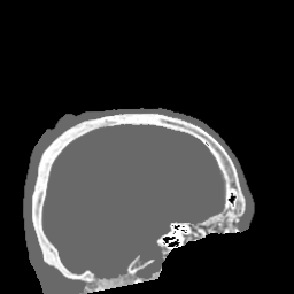

Model-based treatment planning for transcranial ultrasound therapy typically involves mapping the acoustic properties of the skull from an x-ray computed tomography (CT) image of the head. Here, three methods for generating pseudo-CT images from magnetic resonance (MR) images were compared as an alternative to CT. A convolutional neural network (U-Net) was trained on paired MR-CT images to generate pseudo-CT images from either T1-weighted or zero-echo time (ZTE) MR images (denoted tCT and zCT, respectively). A direct mapping from ZTE to pseudo-CT was also implemented (denoted cCT). When comparing the pseudo-CT and ground truth CT images for the test set, the mean absolute error was 133, 83, and 145 Hounsfield units (HU) across the whole head, and 398, 222, and 336 HU within the skull for the tCT, zCT, and cCT images, respectively. Ultrasound simulations were also performed using the generated pseudo-CT images and compared to simulations based on CT. An annular array transducer was used targeting the visual or motor cortex. The mean differences in the simulated focal pressure, focal position, and focal volume were 9.9%, 1.5 mm, and 15.1% for simulations based on the tCT images, 5.7%, 0.6 mm, and 5.7% for the zCT, and 6.7%, 0.9 mm, and 12.1% for the cCT. The improved results for images mapped from ZTE highlight the advantage of using imaging sequences which improve contrast of the skull bone. Overall, these results demonstrate that acoustic simulations based on MR images can give comparable accuracy to those based on CT.